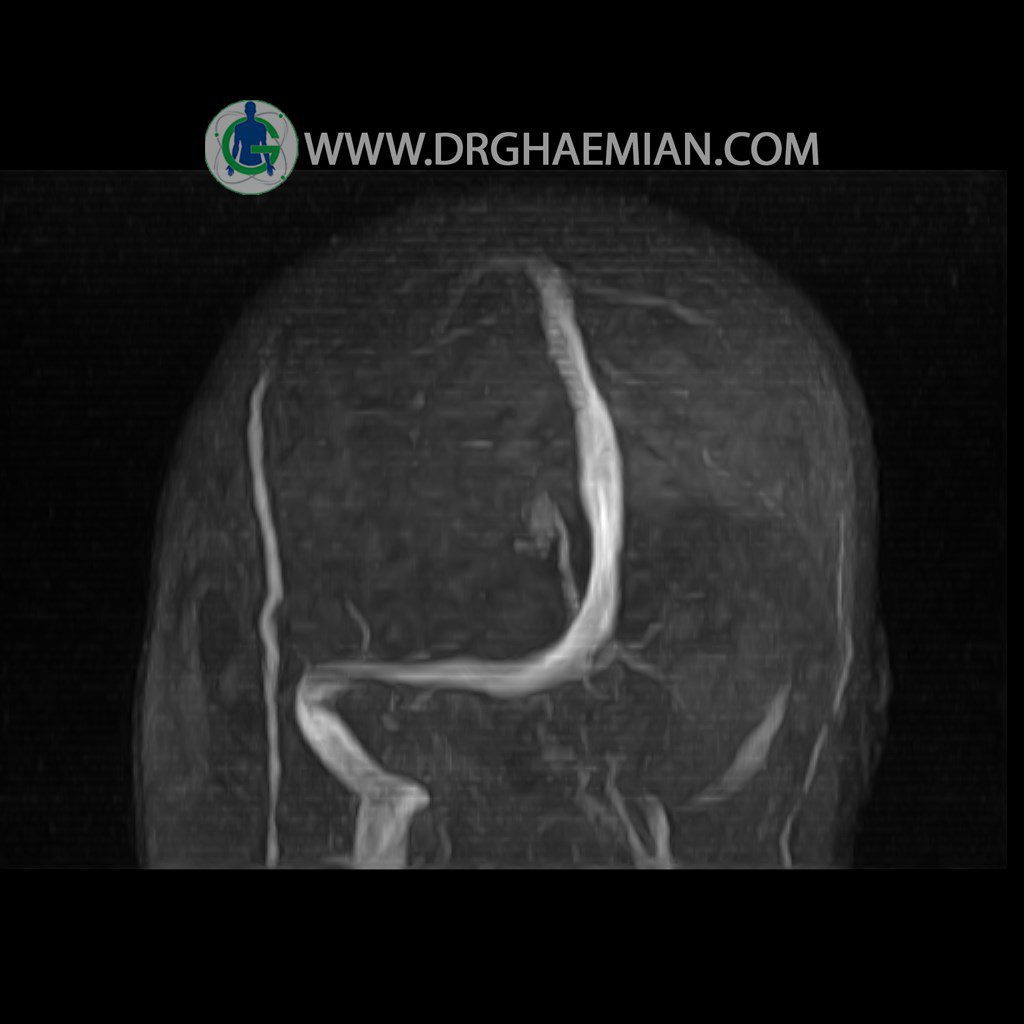

ام آر وی یک روش تصویربرداری دقیق و غیر تهاجمی است که برای معاینه ورید های بدن و ارزیابی سلامت رگ ها استفاده می شود. ورید ها خون را از اعضای بدن به قلب باز می گرداند تا دوباره اکسیژن و مواد مغذی به خون داده شود. ام آر وی جریان خون را ارزیابی و موارد غیرعادی مضر مانند لخته های خونی را شناسایی می کند. در این کیس ترومبوز انسدادی مغز بیمار مشاهده می شود.

CRANIAL MRV

(with & without contrast )

Technique: TOF ( time of flight ).

– Nonvisualized left transverese sinus with narrowing of left sigmoid sinus suggestive for obstructive thrombosis

is seen

COMMENT : in comparison to previous MRI ( 1400/12/09 ) no significant change is seen.